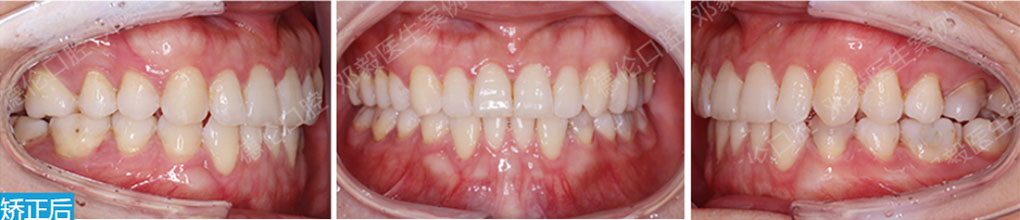

矯治前后對(duì)比

蛻變周期:上頜16個(gè)月,矯治效率提升30%,下頜12個(gè)月,矯治效率提升20%

矯

治

后

口

內(nèi)

照